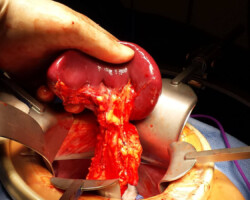

Dr. McCain, winner of the Pancreas Foundation Nobility in Science Award, has seen many pancreatic tumors and his practice. With his experience and expertise in this specialty small tumors of the ampulla are removed via a transduodenal approach while tumors of the head of the pancreas are resected using the Whipple procedure. We have recently seen a significant increase in solid and cystic tumors of the mid body and distal pancreas requiring less extensive resections for removal. Laparoscopy or robotic resection with intra-operative ultrasound is used to detect advanced disease at the start of each operation